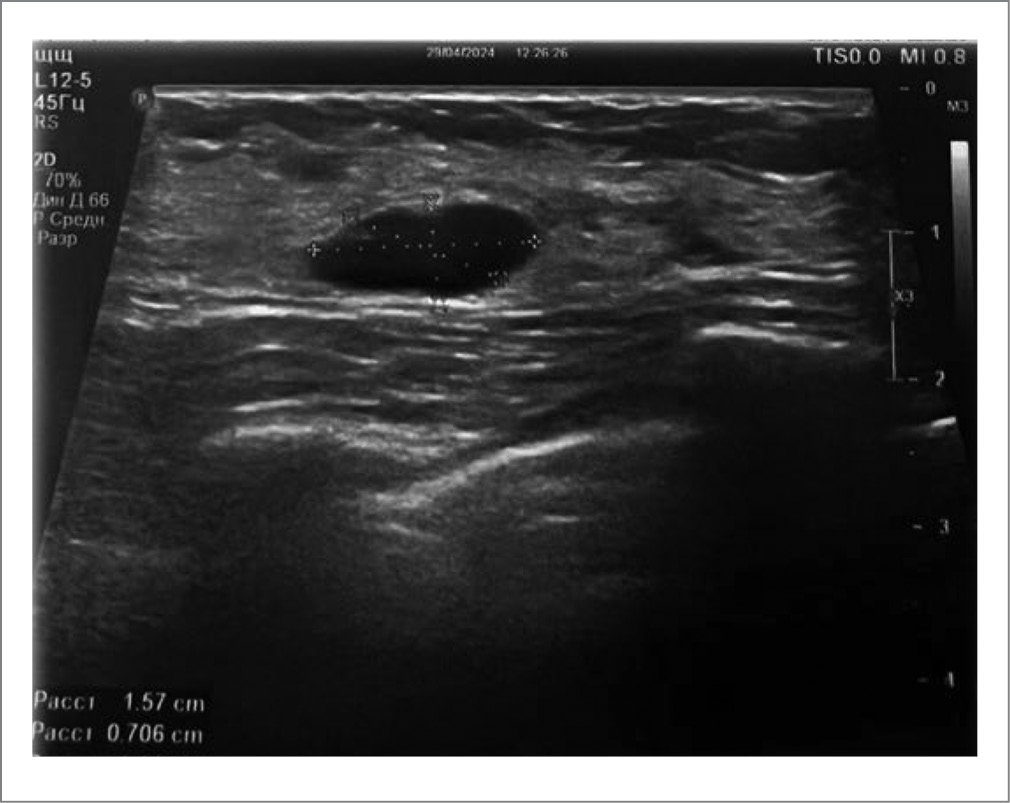

Ультразвуковые параметры ткани МЖ и кистозных образований в МЖ имели также различия между группами после лечения. В частности, до начала лечения в целом у всех пациенток наблюдалось повышение эхоплотности МЖ в сочетании с нерезко выраженной гиперплазией железистой ткани. Спустя месяц после начала терапии препаратом Мастопол® и пневмосклерозирования кист воздушной смесью у больных 1-й группы стала отчетливо прослеживаться тенденция к еще более выраженному уменьшению толщины железистой ткани и эхоплотности, а также уменьшению диаметра кист вплоть до их полного исчезновения; утончение стенок кист. В частности, сравнительный анализ медианных показателей между группами свидетельствовал о достоверном различии эхографических данных между группами (p≤0,001); табл. 1; рис. 1, 2. У женщин 2-й группы, которым проводились только аспирация и пневмосклерозирование без сопровождающей терапии, динамики в изменении структуры железистой ткани, толщины стенок кист, диаметра кист не наблюдалось. Уменьшились в диаметре только те макрокисты, из которых аспирирован экссудат с последующей пневматизацией. При этом утончения стенок кист на обнаружено. Практически всем больным 2-й группы – 89,5% (n=17) – потребовалась повторная пневматизация для полной редукции кист, тогда как в 1-й группе больных повторная пункция с пневмосклерозированием проведена только 31% (n=8) пациенток. Сравнительный анализ демонстрировал достоверное различие между группами: φ*=1,7; p≤0,04.

Рис. 1. Эхография МЖ до пневматизации.

Fig. 1. Echography of the breast before pneumatization.